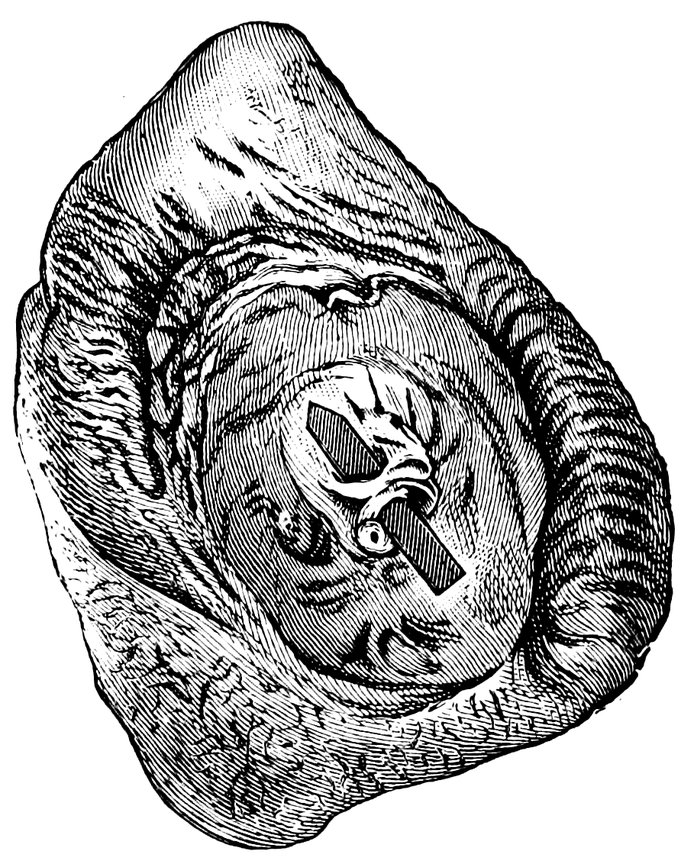

| 18. | Annular Hymen | 64 |

| 19. | Annular Hymen | 64 |

| 20. | Semilunar Hymen | 65 |

| 21. | Annular Hymen with Congenital Symmetrical Indentations | 65 |

| 22. | Fimbriate Hymen | 65 |

| 23. | Deflorated Fimbriate Hymen | 65 |

| 24. | Septate Annular Hymen | 67 |

| 25. | Septate Semilunar Hymen | 67 |

| 26. | Extremely tough Annular Hymen with an obliquely disposed Septum | 67 |

| 27. | Septate Hymen with Apertures of unequal Size | 67 |

| 28. | Septate Hymen with Apertures of unequal Size | 68 |

| 29. | Hymen with rudimentary Septum | 68 |

| 30. | Hymen with posterior rudimentary Septum | 68 |

| 31. | Labiate Hymen with posterior rudimentary Septum | 68 |

| 32. | Hymen with anterior rudimentary Septum | 69 |

| 33. | Hymen with anterior rudimentary Septum projecting in a opiniform Manner | 69 |

| 34. | Hymen with anterior and posterior rudimentary Septa | 69 |

| 35. | Hymen with filiform Process projecting from the anterior Margin | 69 |

| 36. | Hymen in which there are two symmetrically disposed thinned Areas. The left of these is perforated | 69 |

| 37. | Very unusual form of Hymen | 70 |

| 38. | Semilunar Hymen with cicatrized Lacerations in its Border | 70 |

| 39. | Deflorated Semilunar Hymen with laterally disposed symmetrical Lacerations | 70 |

| 40. | Deflorated Annular Hymen with several cicatrized Lacerations | 70 |

| 41. | A. Septate Hymen in which defloration has been effected through one of the Apertures. U. Urethra. Cl. Clitoris. H. Cicatrized Margin. C. Septum. B. Lateral view of Septum | 70 |

| 42. | Deflorated Septate Hymen | 71 |

| x43. | Hymen with larger anterior and smaller posterior Apertures | 71 |

| 44. | Carunculæ Myrtiformes in a Primipara | 71 |

| 45. | Vaginal Inlet of a Multipara, without Carunculæ Myrtiformes. Slight Prolapse of Anterior and Posterior Vaginal Walls | 71 |